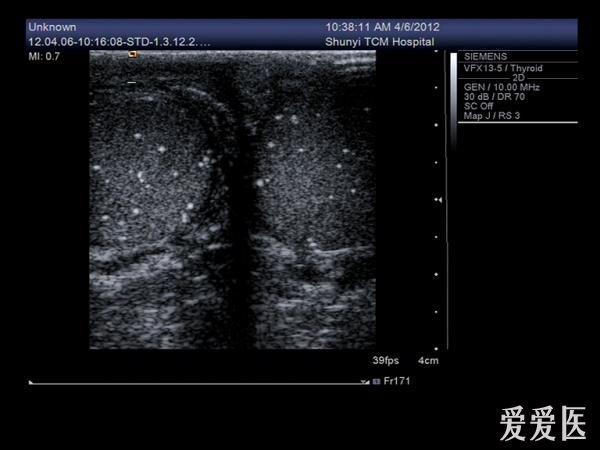

睾丸内点状强回声是什么东西?有图

前几天有个病人来检查,说睾丸疼,大小、形态都没什么变化,就是睾丸内有好多点状强回声,伴彗星尾征。请问这些东西是什么?钙化点?

典型的睾丸微石症

典型的睾丸微石症,有些人和结核有关系!